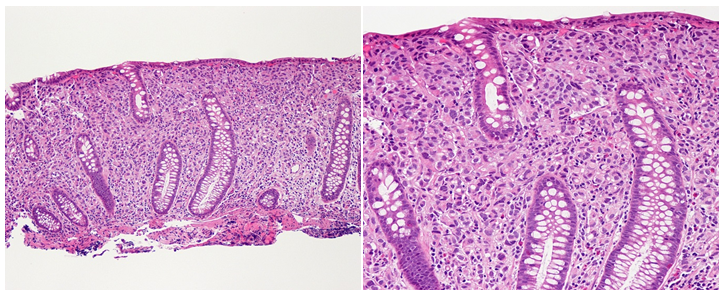

1. 1–74year-old female with a history of breast cancer at the age of 32 treated with mastectomy and radiation, pathology unknown. At age 64, the patient developed Contralateral DCIS, ER/PR+, treated with mastectomy and Anastrozole. At age 70, metastatic spread to lymph nodes, ER/PR+ and HER2- was found. Fulvestrant and Denosumab were initiated after complete staging also found bone metastases. Two years later, she was found to be anemic and colonoscopy revealed small polypoid lesions (she had prior history of adenomatous polyps) with breast cancer visible in colonic crypts, ER+/PR-/HER2- (Figure 1). CEA was elevated at 220 (normal value <5). A CA 27.29 breast cancer associated marker was normal at 18 (normal up to 28). She was treated with Exemestane and Denosumab, but unfortunately succumbed to disease ten months after the diagnosis of gastrointestinal metastases.

Figure 1 Pathology slides from case #1, showing intact crypts with complete replacement of the lamina propria by tumor.